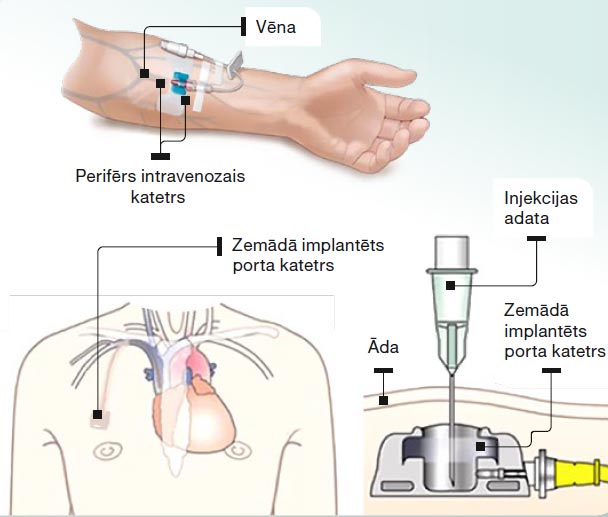

Ķīmijterapija novājina organisma imūno sistēmu, tāpēc dažas nedēļas pirms ķīmijterapijas uzsākšanas rekomendē apmeklēt zobārstu, iziet obligāto vakcināciju, plaušu vēža pacientiem rekomendē vakcinēties pret gripu atbilstošā sezonā un pret pneimokokiem (mikroorganismiem, kas izraisa plaušu infekciju), kā arī vakcinēties pret COVID-19. Pirms ķīmijterapijas uzsākšanas pacientam obligāti nozīmē asins analīzes, novērtē vispārējo stāvokli, aknu un nieru funkciju. Pirms katra nākamā ķīmijterapijas kursa tiek veiktas jaunas asins analīzes, lai ārsts izvērtē, vai drīkst sistēmisko terapiju turpināt pēc plāna vai ir jāļauj organismam nedaudz ilgāk atpūsties. Smēķējošiem pacientiem stingri rekomendē pārtraukt smēķēšanu, jo tā būtiski samazina ārstēšanas efektu. Pieeju ķīmijterapijas ievadei visbiežāk nodrošina caur venozo katetru, ko medmāsa ievieto kādā no rokas vēnām katru reizi pacientam atnākot uz ķīmijterapijas kursu. Ir arī citi intravenozas pieejas veidi, piemēram, zemādā implantējams porta katetrs. Katetram ir rezervuārs, kurā ar adatas palīdzību veic medikamentu ievadi, bet katetra gals savienojas ar lielu vēnu. Porta katetrs tiek ievietots zemādā un netraucē ikdienas aktivitātes, higiēnas procedūras.

Intravenozas pieejas veidi imijterapijas ievadei